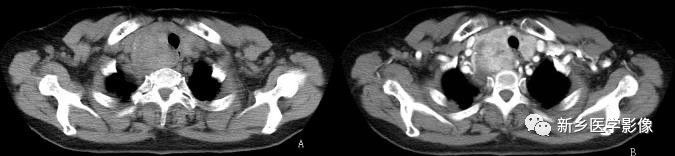

侵袭性胸腺瘤CT图像

a. CT平扫示肺动脉与胸骨间肿块,密度尚均匀,形态不规则b. CT增强示肿块不均匀强化,见低密度囊变区域,肿块与肺动脉之间脂肪间隙消失,肺动脉壁模糊。